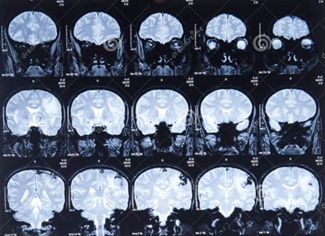

2、层厚(slice thickness)

是由层面选择梯度场强和射频脉冲的带宽来决定的,在二维图像中,层面即是被激发层面的厚度。